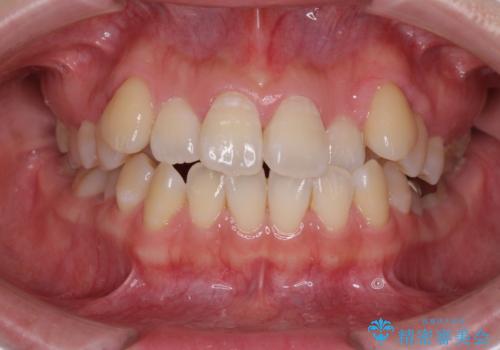

前歯の正中のズレを改善 目立たないワイヤー装置での抜歯矯正

前歯のデコボコを改善 インビザライン矯正

担当医 藤巻太一朗